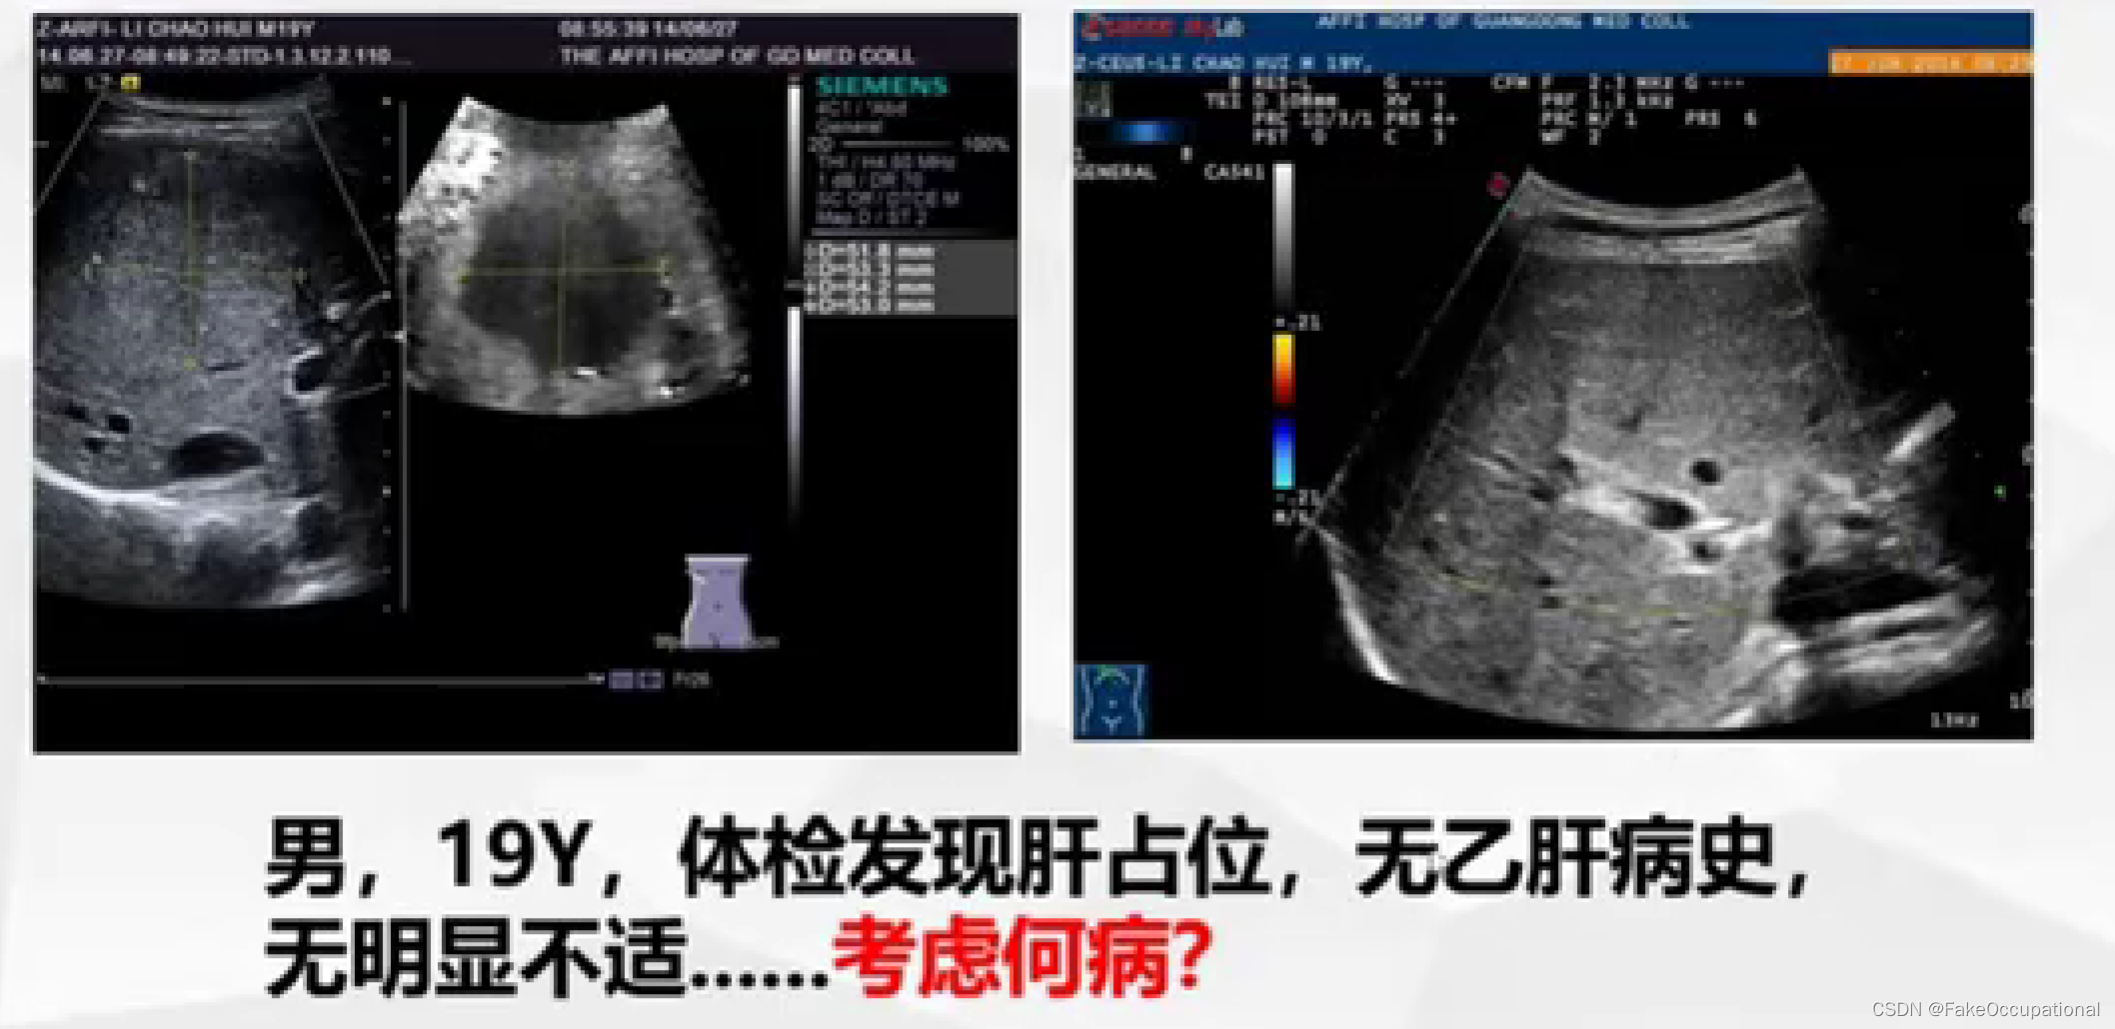

- 超声更多起一个筛查的作用,定性需要造影或者其他设备的辅助